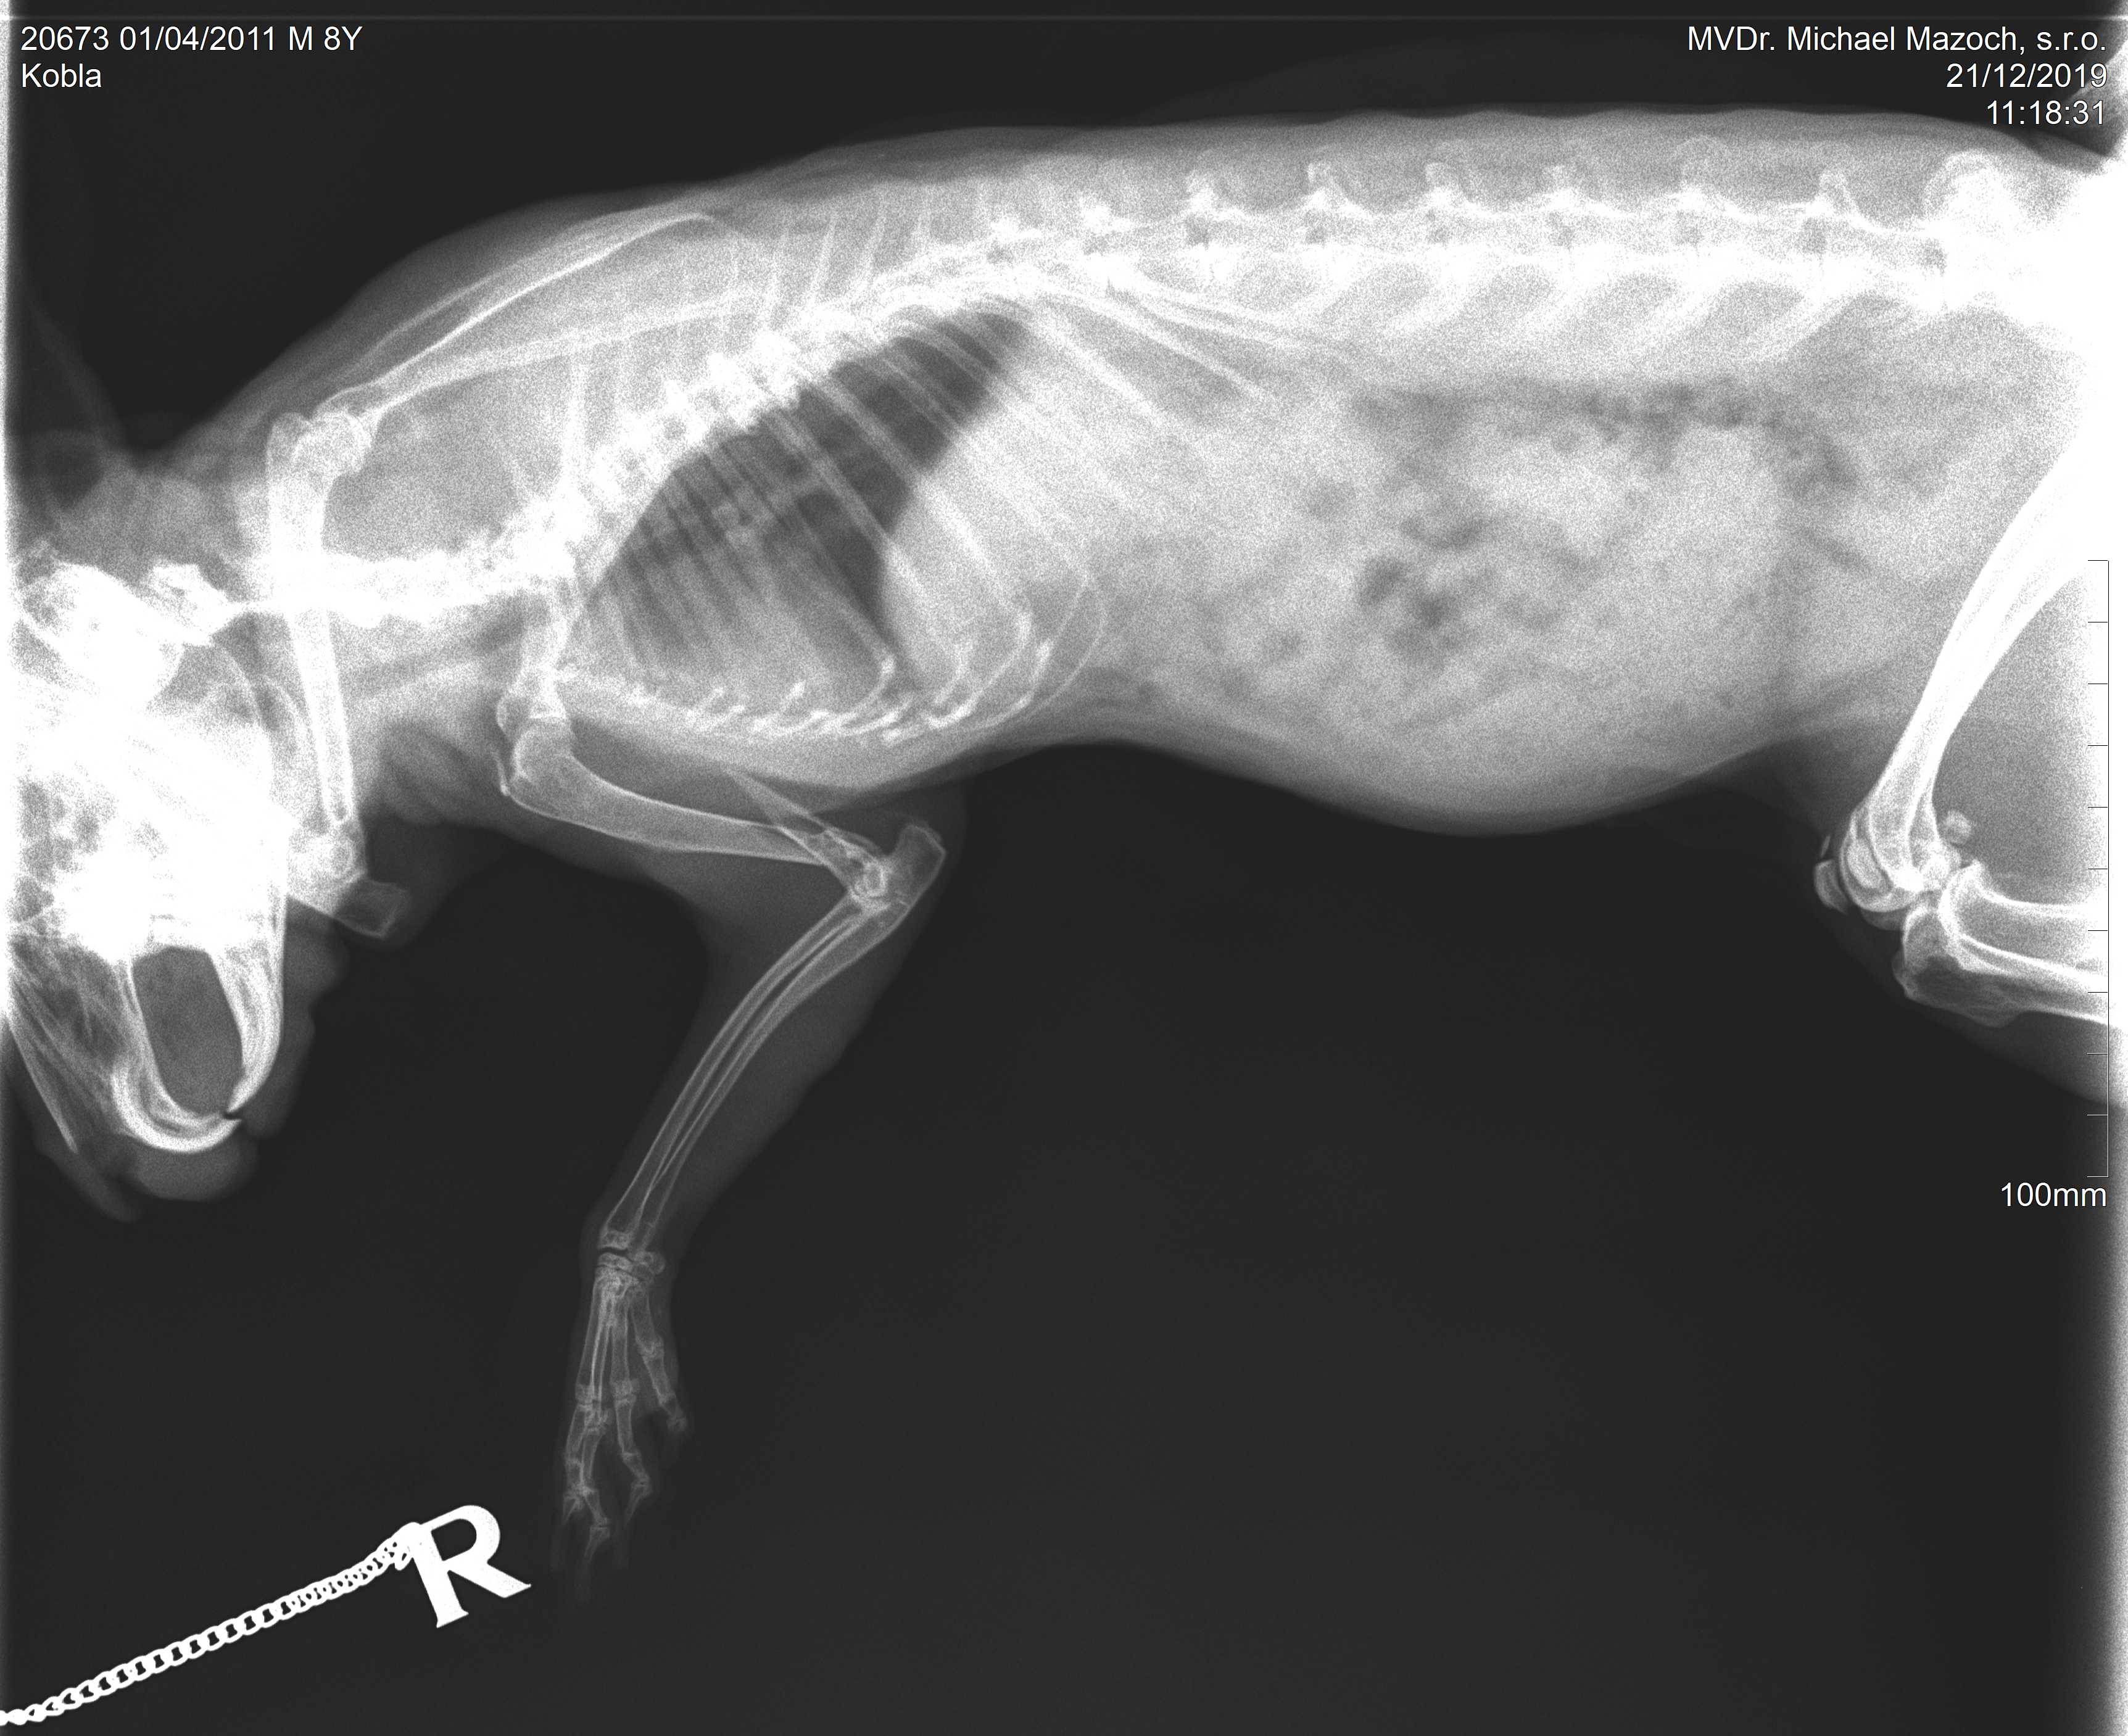

Dobrý den, chtěla jsem se zeptat na váš názor jak postupovat při zlomenině pažní kosti u zakrslého králíka? Zlomenina je čistá ale dle vet na pohotovosti je hodně ostrá a mohla by neustále narušovat okolní svalovinu a tím bránit samovolnému srůstu. Operaci moc postupovat nechceme, králíček má už 9 let a bojím se, že by nepřežil narkózu. Čeká nás návštěva u ortopeda, zatím máme klidový režim a na bolest Meloxoral. Králík má dobrou náladu, nechá se pomazlit, hezky baští i pije. Nožce sám odlehčuje. Děkuji za rady a postřehy. Veronika

Dobrý den. Zlomenina je na špatném místě v dist.části humeru. poblíž lok.kloubu. Samovolný růst k vytvoření svalku., příp.pakloubu by byl dost komplikovaný. Uvidíte , co na to řekne ortopéd. S pozdravem MVDr Jančík.